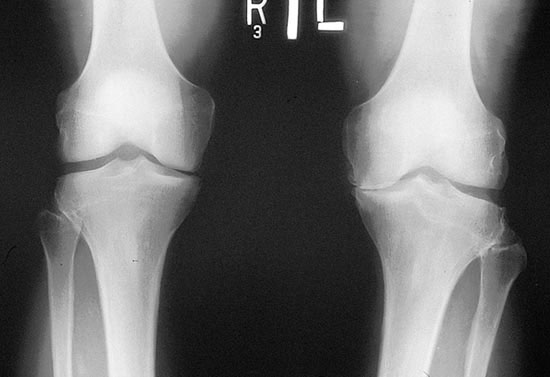

Приходько В.И. врач, МГМСУ, г. Москва По мнению профессора В.В. Поворознюка, Остеоартроз – наиболее распространенная...

Остеохондроз – это дегенеративное поражение межпозвоночных дисков и суставных тканей. В медицине под этим термином...

На сегодняшний день существует огромнейшее количество заболеваний, связанных с суставами. Медицине известны разные формы заболеваний,...